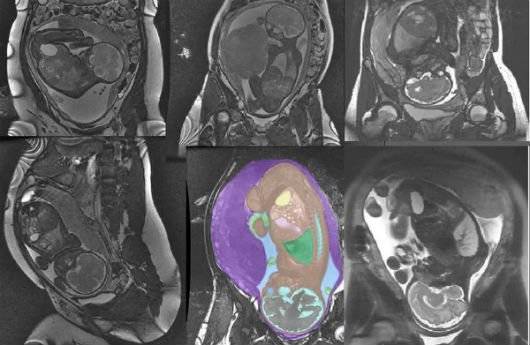

Когда МРТ при беременности не вредно?

Как правило, в первом триместре магнитно-резонансная томография не проводится, так как ее воздействие на формирующийся плод еще не изучено. МРТ назначают только тогда, когда возникает угроза для жизни плода.

Начиная с четвертого месяца МРТ можно делать безбоязненно, так как плод уже сформировался, и процедура не сможет ему повредить. Поэтому, когда врач назначает процедуру после 12 недель, волноваться не о чем.

Женщинам в положении МРТ назначают обычно по нескольким причинам:

- если невозможно проведение других более агрессивных процедур;

- если во время УЗИ на позднем сроке положение ребенка плохо просматривается, что возможно в связи с избыточной массой тела женщины.

Как правило, беременные женщины направляются на МРТ, когда есть подозрения на новообразования и патологии в развитии ребенка. МРТ также может проводится при травмах, повреждениях позвоночника, сердечно-сосудистых заболеваниях, нарушениях в области центральной нервной системы. Когда пациентки испытывают сильные головные боли, им назначается МРТ головного мозга при беременности.

Расшифровка МРТ

Поскольку вы уже знаете, можно ли делать МРТ при беременности, и что опасности на поздних сроках точно нет, важно понять, что часто именно эта процедура может дать полное представление о заболевании. Расшифровка не потребуется, так как все отражается на снимке, и врач быстро понимает в чем проблема.

Возможности магнитно-резонансной томографии

Если МРТ при беременности на ранних сроках лучше избегать, на поздние результаты будут хорошо видны, как у плода, так и у матери. Поэтому важно вовремя провести обследование, когда:

- есть вероятность возникновения патологий у ребенка;

- подозрение на злокачественные опухоли у матери;

- нарушена работа ЦНС;

- есть травмы;

- заболевания сердца;

- неправильно работает ЖКТ.

Возможно, что только МРТ-обследования, которые не опасны на поздних сроках может выявить аномалии и предотвратить серьезные заболевания или рождение больного ребенка.